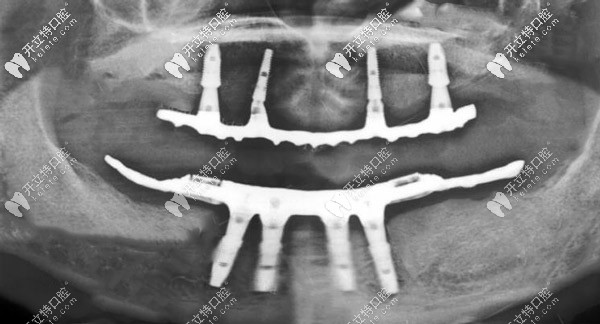

CBCT線片圖▼

ALL-ON-4種植X線片

從種完牙的圖片可以看出,種植假牙比有的真牙還要好看,當(dāng)然種植牙的咬合力也是比較逼近自然牙齒的,而且有了種植體的支撐可以有效緩解牙齦的吸收。